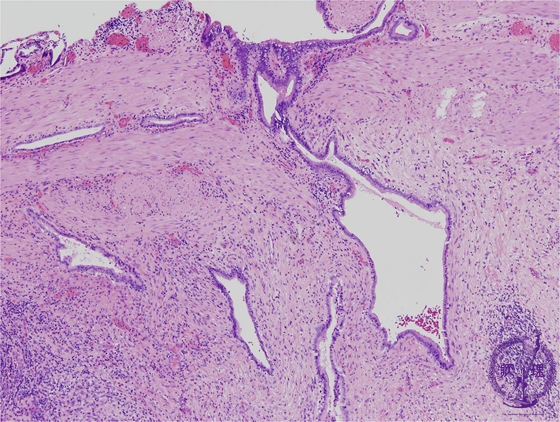

Microscopic image(HE stain, intermediate power):A (Rokitansky-Aschoff) sinus is observed as an invagination of the mucosa through the muscularis, into the subserosa. Nearby, there is fibrosis and a chronic, predominantly lymphocytic infiltrate.